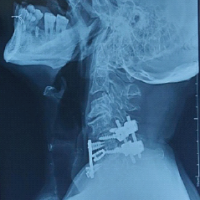

Considering that the ruptured tendon due to bone avulsion did not escape to the proximal A4 pulley, only a distal incision was made at first. However, after exploration, it was determined that the A4 pulley was ruptured and the tendon was advancing proximally. Then, a mini-incision was made over the A1 pulley. The ruptured tendon was found at the proximal border of the A1 pulley (Fig. 2). The tendon was identified, mobilized, and delivered distally through the pulley system using a silicone rod to avoid damaging the intact pulleys and to facilitate gliding (Fig. 3). After preparing the FDP insertion site in the distal phalanx, the tendon was fixed using a 2.5 mm mini anchor suture (Fig. 4). Since the tendon tension was appropriate, no lengthening procedure was considered for the tendon (Fig. 5). The A4 pulley was repaired with 4/0 surgical suture. The flexor tendon sheath and skin were meticulously closed.

Figure 4: Confirmation of anchor placement with fluoroscopy.

Figure 5: Demonstration of pre-operative and post-operative tendon tension.